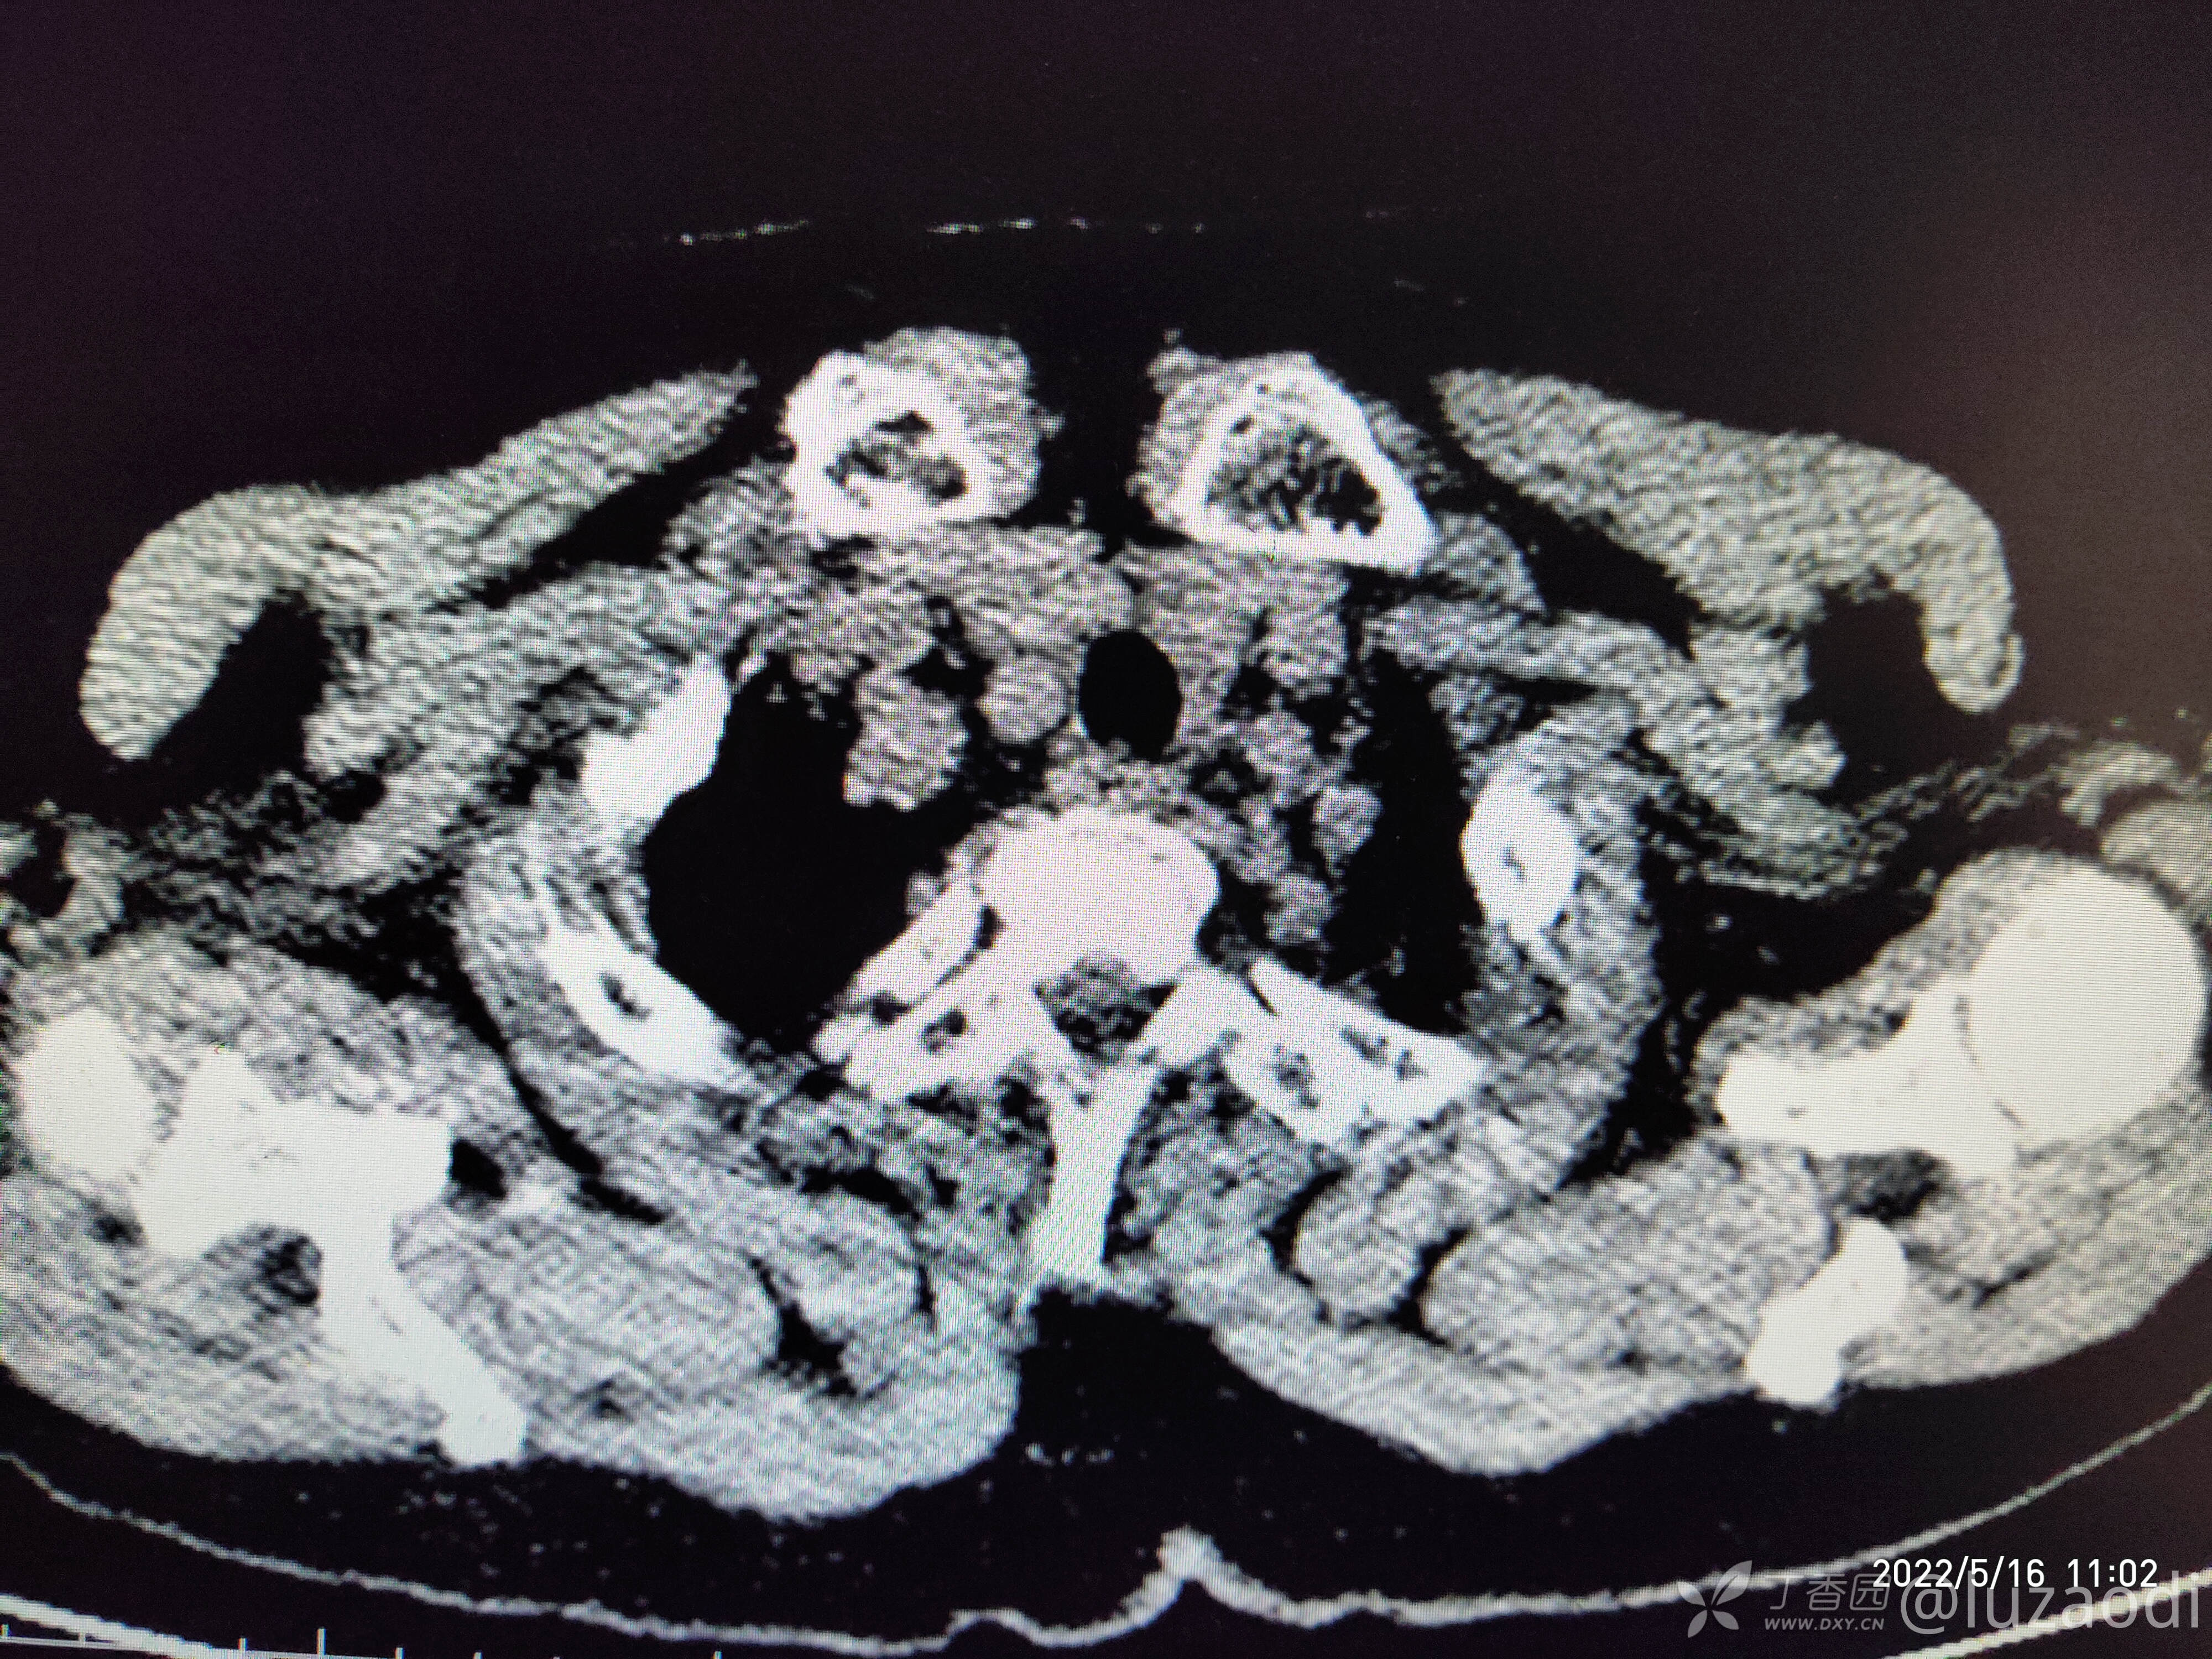

治疗经过:入院后患者仅有乏力,未见明显神经定位征。近期无发热、咳嗽、腹泻症状。遂予血糖、心电图、生化检查及影像检查,结果如下:

我去。。。。。视频只能上传一个,头颅CT上传不了,我直接说报告吧。头颅CT报腔隙性脑梗。